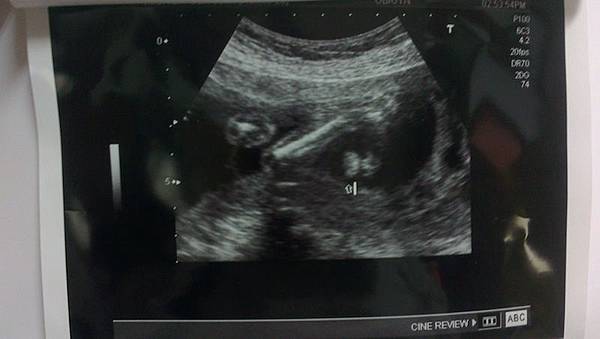

早上8:30到醫院先照超音波,確認寶寶的狀況,19W3D這天,寶寶重313克(三週前是180克),測量出寶寶的大小剛好是19w3d,很標準呢

這次懷孕,自17周開始,每天整天很容易感覺到胎動,記得上次懷瀚瀚時,並沒有這麼明顯感覺,這次自第一次產檢到現在,每次照超音波,都可以看到小手小腳揮來揮去,這次則是看到兩隻小手抓握,然後兩手放在頭上,看來是個很活潑的小孩呢(慘了到時我要怎麼對付兩個小男生。。。

再次確認後,是男生

確認寶寶的心跳ok,下圖左邊是從屁股下方看上去,再次確認是男生。。。右邊可以很清楚看到手指

下圖箭頭所指的是鼻孔跟嘴巴,主要是看有沒有唇顎裂如果左邊的嘴唇都是白色顯影的,表示正常,反之這個檢查很重要喔,上次瀚瀚沒檢查到這項呢